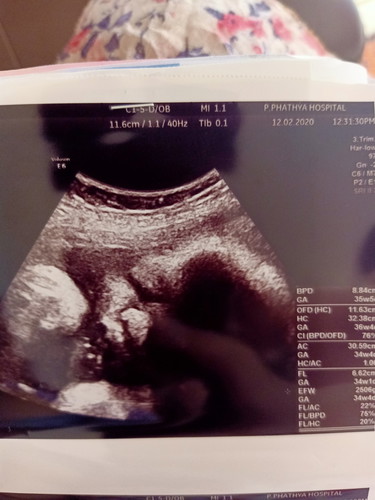

บ้านนี้ 34+3 วีค ลูกหนัก 2,506 กรัม บ้านอื่นหนักเท่าไรกันแล้วคะ เล่าสู่กันฟังบ้างค่ะ